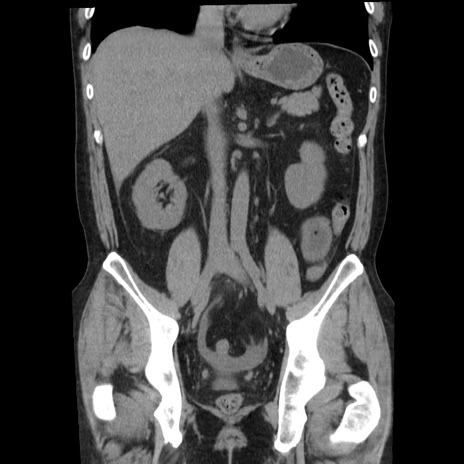

症例29(冠状断像)

【症例】40歳代男性

【現病歴】2日前から胃痛あり。徐々に周期的な激痛に変化した。本日になっても激痛があるため受診。

【身体所見】意識清明、BT 38-39℃台あり、腹部:膨満、やや硬、右下腹部に圧痛あり。

【データ】WBC 8500、CRP 23.26